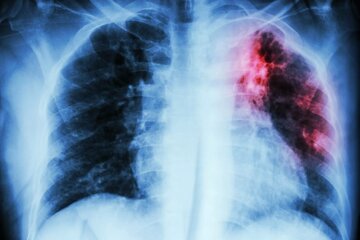

سل یک بیماری عفونی شایع و در بسیاری از موارد مرگبار است. این بیماری توسط گونههای مختلف مایکوباکتریا و به طور معمول «مایکوباکتریوم توبرکلوزیس» ایجاد میشود.

علائم کلاسیک عفونت سل فعال عبارت از سرفه مزمن با خلط آغشته به خون، تب، تعریق شبانه و کاهش وزن هستند.